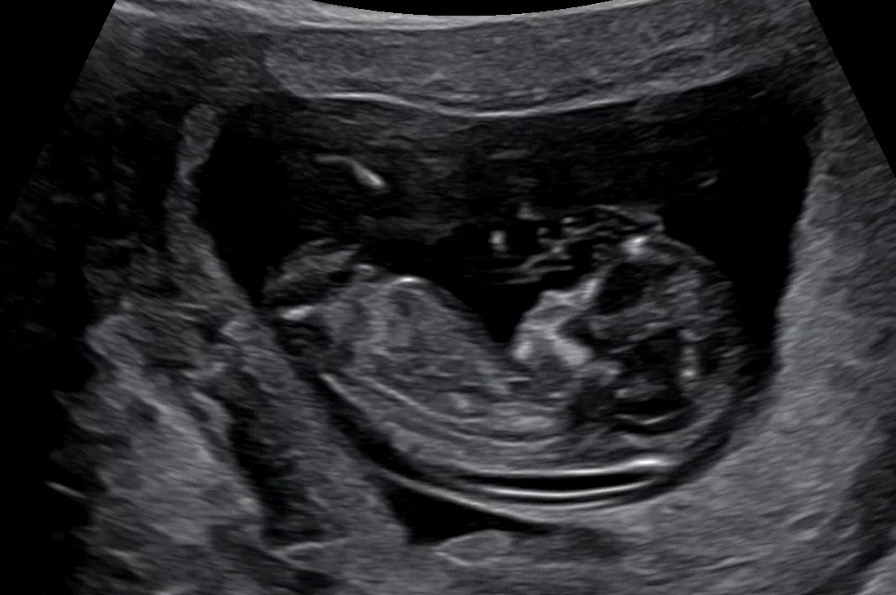

재미로 보는 각도법쓰

둘째예유 각도법 봐주실래욘?ㅎㅎ감사해여 재미나이가 딸이라고했는데 과연… 4주 어떻게 기다려요? ㅠㅠㅠㅠ